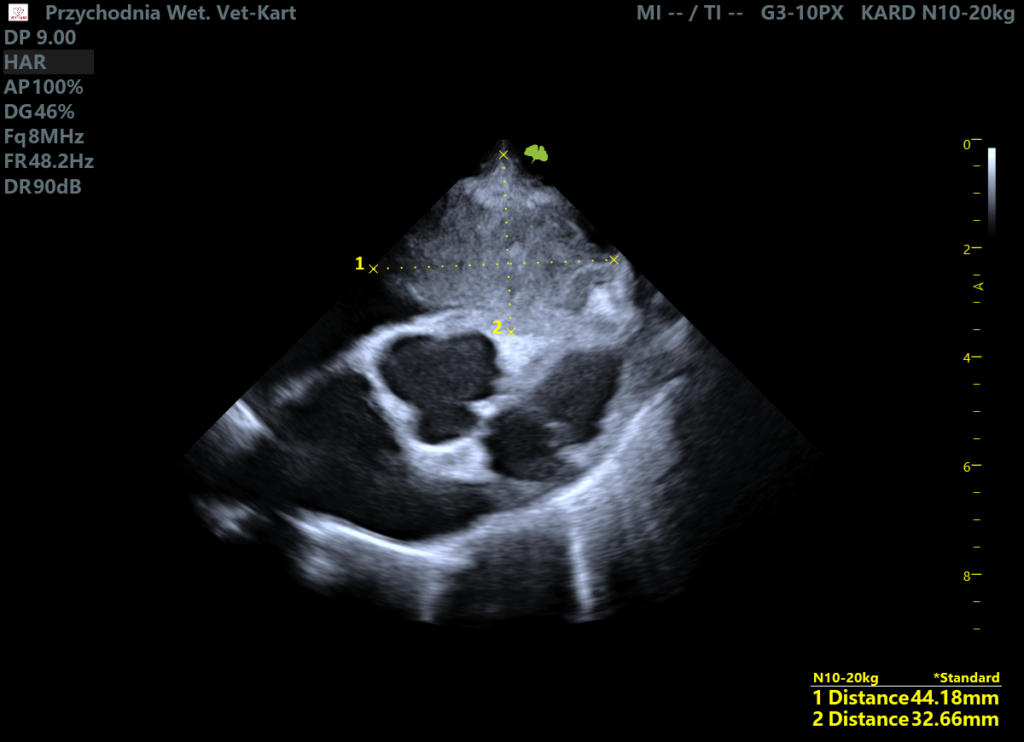

Wykonano badanie echo serca:

Kluczowym znaleziskiem była dobrze zdefiniowana, niejednorodna, hipoechogenna względem wsierdzia zmiana o wymiarach 4,4 × 3,3 cm, zlokalizowana na wysokości zastawki trójdzielnej, związana z jej płatkiem/pierścieniem. Masa poruszała się synchronicznie z ruchem zastawki i powodowała częściową obstrukcję.